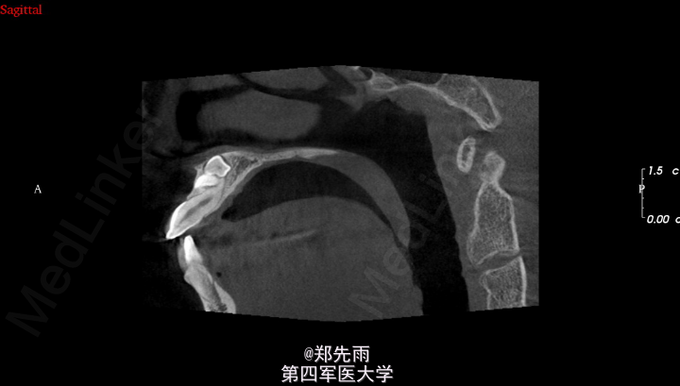

前牙区埋伏牙+上颌窦气化严重

13先天性埋伏阻生,前鼻棘下方埋伏牙,行CBCT检查提示均位于唇侧,但CBCT提示双侧上颌后牙牙根不同程度位于上颌窦内。

诊断:13埋伏阻生,上颌埋伏多生牙。 处理:住院拔除上颌埋伏牙,分次拔除正畸减数牙。与患者术前充分沟通上颌窦穿孔、上颌窦瘘的可能。